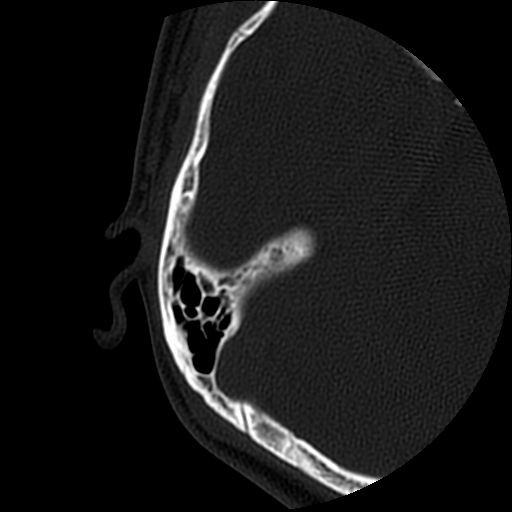

以下是引用随光逐影在2009-8-19 7:25:00的发言:[br]右侧慢性中耳乳突炎,右侧中耳腔及外耳道肉芽肿或胆脂瘤形成。